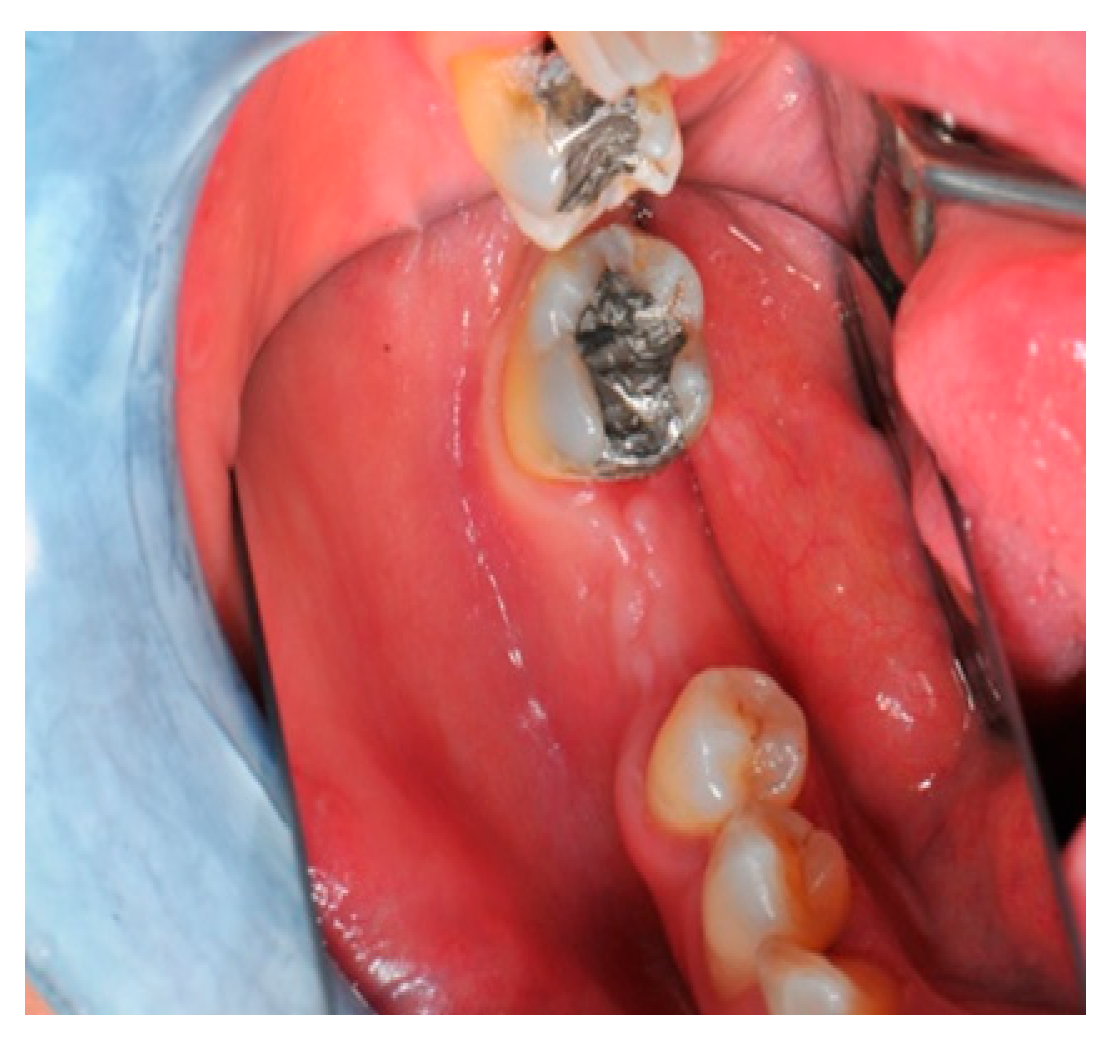

- Flap design: Soft tissue management should be as accurate as possible. The design of the flap should ensure a tension-free primary closure of the wound even after voluminous grafting of the defect. One option (preferred especially in wide vertical defects) is the execution of the so-called “poncho” flap. This technique includes a high vestibular incision of the mucosa, muscle and periosteum in order to undermine the preparation of the flap and to achieve its mobilization, followed by a deep incision in the buccal area with two additional vertical incisions that are performed at an appropriate distance from the occlusal area and the site of augmentation. After the incision, the preparation of a muco-periosteal flap and the remotion of scar tissue, a full thickness flap is raised until the bone defect is uncovered [17,18,19,20]. Finally, the positioning of the customized titanium mesh is passively tested to evaluate its fit intra-operatively (Figure 2, Figure 3, Figure 4 and Figure 5).